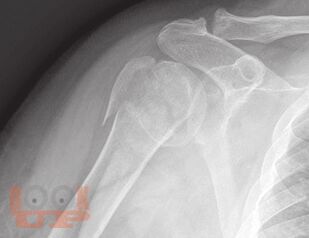

В пособии рассматриваются различные заболевания и травмы конечностей в аспекте их выявления лучевыми методами. Пособие составлено с учетом комплексного подхода к патологиям (костей и мягких тканей, суставов, сосудов, нервов) и диагностических методов (классического рентгеновского, КТ, МРТ, ультразвукового).